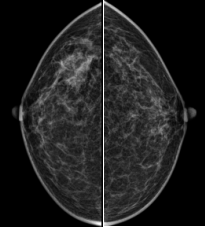

乳腺X线照相(Mammography,MG,也即是咱们常说的“钼靶”),是乳腺癌筛查的紧迫妙技之一。传统的通例乳腺X线照相属于平片成像,它就像把扫数这个词乳腺组织投影在一个平面上,图像存在堆叠效应。这就可能导致明明莫得肿瘤,却因组织的相互讳饰看起来像有肿瘤体育游戏app平台,或者明明存在肿瘤,却因被其他组织覆盖而无法发现,容易变成误诊、漏诊等情况。

而我院新引进的联影-嫦娥uMammo890i钼靶机,搭载了翻新uMammo时刻,让乳腺筛查愈加精确、安全、高效。

高清影像“微”不雅病变

该成立领受高差异率平板探伤器与智能图像处分算法,犹如领有了一对“知秋一叶”。随机发现微细钙化灶、使得部分早期病变也无法遁形。它为乳腺癌的早诊早治提供了有劲援手,匡助临床医师精确捕捉病灶。